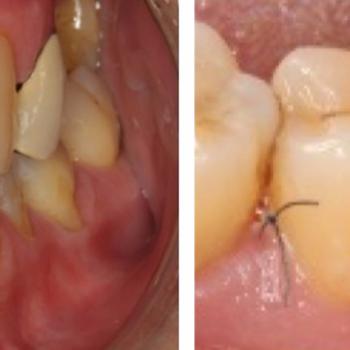

Regeneración de un defecto periodontal más allá del ápice de un molar inferior mediante el uso de hueso autólogo y membrana no reabsorbible de PTFE

Os presentamos un nuevo caso clínico que nos llega desde el Departamento de Periodoncia de la Facultad de Odontología de la USC. Se trata de una espectacular regeneración periodontal de un defecto infraóseo más allá del ápice de un molar inferior mediante hueso autólogo y membrana no reabsorbible con seguimiento hasta los dos años. Como manifiestan sus autores, si se escoge muy bien el caso, la regeneración periodontal parece no tener límites.